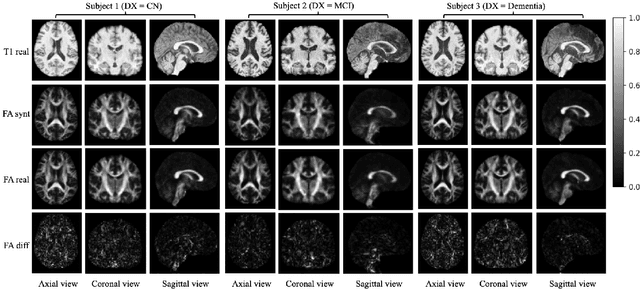

Abstract:Diffusion tensor imaging (DTI) provides crucial insights into the microstructure of the human brain, but it can be time-consuming to acquire compared to more readily available T1-weighted (T1w) magnetic resonance imaging (MRI). To address this challenge, we propose a diffusion bridge model for 3D brain image translation between T1w MRI and DTI modalities. Our model learns to generate high-quality DTI fractional anisotropy (FA) images from T1w images and vice versa, enabling cross-modality data augmentation and reducing the need for extensive DTI acquisition. We evaluate our approach using perceptual similarity, pixel-level agreement, and distributional consistency metrics, demonstrating strong performance in capturing anatomical structures and preserving information on white matter integrity. The practical utility of the synthetic data is validated through sex classification and Alzheimer's disease classification tasks, where the generated images achieve comparable performance to real data. Our diffusion bridge model offers a promising solution for improving neuroimaging datasets and supporting clinical decision-making, with the potential to significantly impact neuroimaging research and clinical practice.